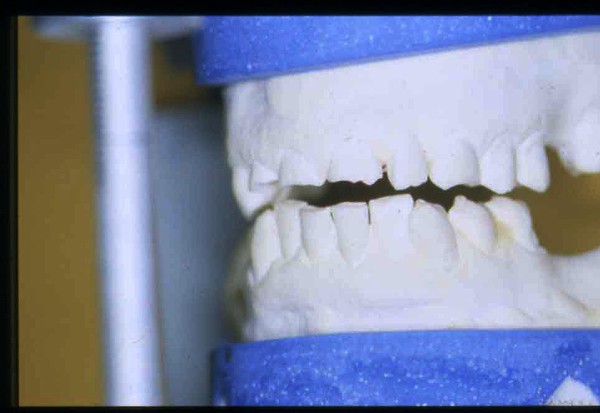

APRECIACIONES DIAGNÓSTICAS EN BASE A LA APERTURA MENTAL DEL CLÍNICO FRENTE A LO QUE EL PACIENTE PROPONE EN MUCHAS OCASIONES , LA DEMANDA DE LOS PACIENTES NOS INCLINAN A FOCALIZAR NUESTRA ATENCIÓN EN LAS PIEZAS DE LAS CUALES EL ENFERMO SE QUEJA. PACIENTE SEXO FEMENINO, 55 AÑOS, SE PRESENTA A LA CONSULTA DERIVADA POR COMPAÑERO GENERALISTA, QUIEN LLEVA MESES PROCEDIENDO A LA «DESINFECCIÓN» DE UN PRIMER PREMOLAR IZQUIERDO, EL QUE SE PRESENTA ABIERTO EN SU CONDUCTO EN EL AFÁN DE PERMITIR EL ESCAPE DE GASES DE UNA GANGRENA PULPAR. A LA INSPECCIÓN CLÍNICA SE OBSERVAN FACETAS PARAFUNCIONALES DE TERCER GRADO , ASINTOMÁTICAS, CON EVIDENTES DIFICULTADES MASTICATORIAS Y ESTÉTICAS , FALTA TOTAL DE SUS MOLARES INFERIORES, Y ADELANTAMIENTO PRONUNCIADO DE SU MANDIBULA, LA QUE CUESTA MANIPULAR DEBIDO A LA SITUACIÓN DE ESPASMO DE CASI TODA SU MUSCULATURA GNATICA. SE ESTUDIA EL CASO RADIOLOGICAMENTE, Y SE RELAJA EL SISTEMA MEDIANTE LAM. DE LONG REALIZANDO UN MONTAJE EN LA ORC OBTENIDA. NO SATISFECHOS CON EL RESULTADO, CONFECCIONAMOS UN JIG DE LUCIA, EL QUE DEJAMOS EN BOCA TODA UNA NOCHE, AL CABO DE LA CUAL REALIZAMOS UN NUEVO REGISTRO REALIZAMOS UN ENCERADO RÁPIDO DEL CASO, Y CONFECCIONAMOS UNA ESTRUCTURA OCLUSAL PLASTICA, QUE ADEMÁS REPONGA EL ASPECTO ESTÉTICO PERDIDO (FÉRULA DE RELAJACIÓN DE COMPONENTE ESTÉTICO), LO QUE PERMITE AL ENFERMO LUEGO DE DOS DÍAS DE USO, NO SOLO CORROBORAR LA COMODIDAD MASTICATORIA Y LA FALTA DE SÍNTOMAS MUSCULARES, SINO TAMBIÉN OBSERVAR APROXIMADAMENTE LA DIFERENCIA ENTRE LA SITUACIÓN INICIAL Y LO QUE PUEDE LOGRARSE MEDIANTE EL TRATAMIENTO. EL PACIENTE ADVIERTE LA MEJORÍA DE LA SITUACIÓN. ACEPTADO POR PARTE DEL MISMO EL TRATAMIENTO SUGERIDO, CREAMOS UN JUEGO COMPLETO DE PROVISORIOS EN BASE AL ENCERADO, Y PROCEDEMOS A TRATAR LA INFRAESTRUCTURA, QUE CONSISTE EN LAS ENDODONCIAS, SUS REFUERZOS A PERNOS DE ORO, LOS ASPECTOS PERIODONTALES DEL CASO, Y DOS IMPLANTES INFERIORES CON TÉCNICA SEMISUMERGIDA ,DE 5 MM DE ANCHO POR 12 DE LONGITUD, CON ANILLO DE ZIRCONIO , A LA ESPERA DE OSTEOINTEGRACIÓN, TRANSCURREN TRES MESES EN EL USO DE UNA NUEVA OCLUSIÓN CONSTITUIDA POR LOS PROVISIONALES, SEGÚN EL ENCERADO, QUE SE REALIZÓ SIGUIENDO LOS CÁNONES DE UNA OCLUSIÓN ORGÁNICA. COMPROBADA LA EFICACIA DE LA NUEVA SITUACIÓN, CON SUS DISCLUSIONES LATERALES Y POSTERO ANTERIORES CORRECTAS, CARECIENDO YA DE SINTOMATOLOGÍA MUSCULAR (SIN MIALGIAS, SIN MIOSITIS, Y CON UN GRADO DE APERTURA DE 4,50 CM), Y SIN SIGNOS EVIDENTES DE DESGASTE SOBRE EL MATERIAL DE LOS PROVISORIOS, ES DECIR: VERIFICANDO QUE EL PACIENTE YA NO BRUXA, VERTICALIZANDO EL CICLO MASTICATORIO /OTORGANDO ORC/ DIMENSIÓN VERTICAL /PROTEGIENDO A LAS PIEZAS `POSTERIORES DE IMPACTOS LATERALES RECIEN ENTONCES , MONTAMOS EN ARTICULADOR SEMI AJUSTABLE LOS MODELOS DE TRABAJO DEFINITIVOS. CONFECCIONAMOS ENTONCES LAS COFIAS INFRA PORCELANA, EN PORCELANA DE ALTA DENSIDAD EN EL SECTOR ANTERIOR Y EN ORO GALVÁNICO PARA EL SECTOR POSTERIOR PARA LUEGO COMPLETAR LA GUIA ANTERIOR , VERIFICANDO LA ALTURA DE LOS INFERIORES RESPECTO DEL LABIO INFERIOR Y CORROBORANDO LOS PUNTOS DE CONTACTOS INTER CANINOS, QUE CENTRALIZAN LA MANDIBULA Y VERTICALIZAN EL CICLO MASTICATORIO Y LAS DISCLUSIONES CANINAS QUE OTORGARÁN PROTECCIÓN A LOS SECTORES POSTERIORES. POSTERIORMENTE CHEQUEAMOS LA DISCLUSIÓN EN PROPULSIVA DE LA GUIA ANTERIOR YA TERMINADA. FIG38 FIG39 UNA VEZ OBTENIDO UN COMANDO ANTERIOR EFECTIVO, COMO LO ES LA GUIA ANTERIOR CON TODOS SUS COMPONENTES, PROCEDEMOS A REALIZAR LAS TABLAS PREMOLAR / MOLAR DE AMBOS LADOS Y OBSERVAMOS QUE LOS PUNTOS INTEROCLUSALES DE CONTACTO SEAN SUFICIENTES Y CUMPLAN SU OBJETIVO DE OTORGAR ESTABILIDAD MESIO DISTAL Y VESTÍBULO LINGUAL. TRANSCURRIDO UN AÑO DE FINALIZADO EL TRATAMIENTO, REALIZAMOS UN CHEQUEO POST OPERATORIO DEL CASO, EN TODOS LOS PARÁMETROS ANTERIORMENTE MENCIONADOS, Y OBSERVAMOS LA ABSOLUTA ESTABILIDAD DEL MISMO EN TODOS SUS NIVELES Y TEJIDOS.